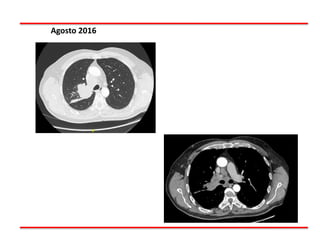

TAC Tórax : 08/16

Masa Pulmonar

Derecho (Lesión

Broncogénica 1ª)

LN Mediastinicas

Agosto 2016